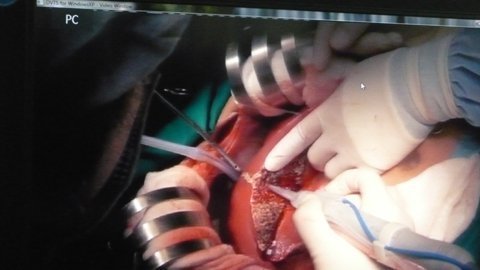

| Các bác sĩ đang thực hiện phẫu thuật. |

Ca phẫu thuật diễn ra từ lúc 8h25p tới 22h30p ngày 12/10, dưới sự

phối hợp nhịp nhàng của các bác sĩ Bệnh viện Chợ Rẫy và 15 y, bác sĩ (4 phẫu

thuật viên, điều dưỡng, bác sĩ gây mê, chẩn đoán hình ảnh, bác sĩ chăm sóc hậu

phẫu…) của Trung tâm ghép gan Asan.